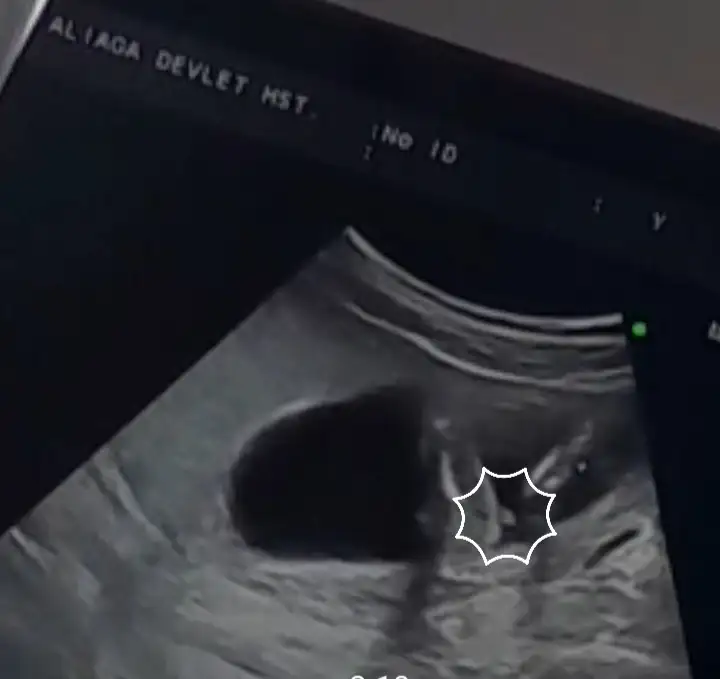

Parlak alabalık göre bakılıyor normalde ama sendeki parlak alan çok ortada kalmış hani tam bir şey diyemiyorum. İlla bir tahmin yapacak olsam onu da şuna göre yapayım, kese yuvarlak gibiyse erkek oluyormuş, fasulye gibiyse kız diyorlar. Tabii doğrululuk payını bilemem burada gördüm, benim kesimde fasulye gibi ama daha cinsiyeti belli değil. 16+5 gündeyiz ayrıntılı ultrasonda belli olacak nasip olursa. Benim bıraktığım ultrasonda parlak alan bir yerde bakınca dizde göreceksiniz hatta tam sol kısımda ve karından çekildi. Karından olduğu için ayna görevi görüyormuş diyorlar. Yani karından ultrasonda sol kısımdaysa aslında parlaklık sağda oluyormuş vs. Bu da erkek bebek demekmiş. Vajinalda ise direk düz gözüktüğü için parlak alan soldaysa kız, sağdaysa erkek. Sonuçlarımız çıkınca bu kese yapısını konuşuruz yine. Kese yapısına göre sizin erkek gözüküyor ama ramziyi anlamadım parlak alan ortada kalmış. Benim için keseye göre kız, ramziye göre erkek. Nub için 11 hafta 13 hafta arası olması lazım ama onda da belli değil bende. Sizinde 11 haftanızda belli olmazsa ultrasonu atarsınız ona da bakarız.

Bu da benim bahsettiğim ultrason resmim.